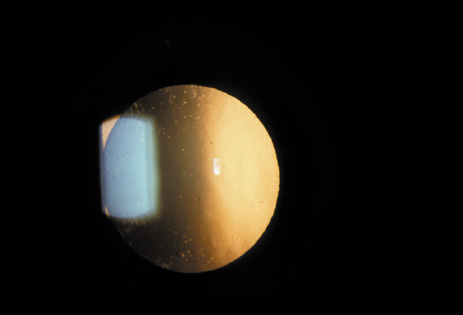

The PSC is the least prevalent subtype in most population-based studies.18 These cataracts often occur in combination with nuclear or cortical cataracts in the later stages. They are easily noticed on retroillumination because they are usually located centrally, and may interfere with funduscopy (Fig. 12). In early stages, patients usually complain of subjective symptoms such as glare disability32 and difficulty focusing on near objects. This is because when the pupil constricts during accommodation, the light entering the eye becomes concentrated centrally, where the PSC is also located. This causes light scattering and interferes with the ability of the eye to focus an image on the macula. In addition, these opacities lie at or near the nodal point of the eye, further interfering with focusing of the image on the macula.

Fig. 12. PSC. Note the central location, which gives rise to severe glare disability.

One can examine this type of cataract with direct illumination, using the narrow and broad beams of the slit-lamp to show the characteristic granular inner surface immediately in front of the posterior capsule (Fig. 13). The problem with this technique, however, is that patients may not tolerate any prolonged direct illumination because of the glare. Retroillumination is therefore more useful for revealing the outline of the opacity, since it is usually seen as an “island” in the center of the posterior capsule, which is further highlighted by the shadow cast by the opacities.33 However, in the early stages of this type of cataract, the dust-like particles that might be noticeable in the central posterior subcapsular area with direct illumination disappear or are difficult to see with retroillumination (Fig. 14). Eventually this “dusting” becomes dense enough to cast a shadow and thus appear on retroillumination. The smooth orange background of the fundus helps to highlight the rough, irregular pseudopodia-like edges of the central opacity. In advanced stages, the PSC may become a thick, calcified plaque (Fig. 15). During surgery, excessively vigorous scraping or vacuuming of the calcified opacity can lead to rupture of the posterior capsule. Usually, small remnants that are left behind after surgery are reabsorbed and do not interfere with vision; otherwise, they are easily treated with a neodymium : yttrium (Nd:YAG) aluminum garnet laser. Pathologic evidence suggests that most PSCs result from the migration of bow region cells into the potential space (along with accumulated cellular debris) between the posterior capsule and the cortex.34–36